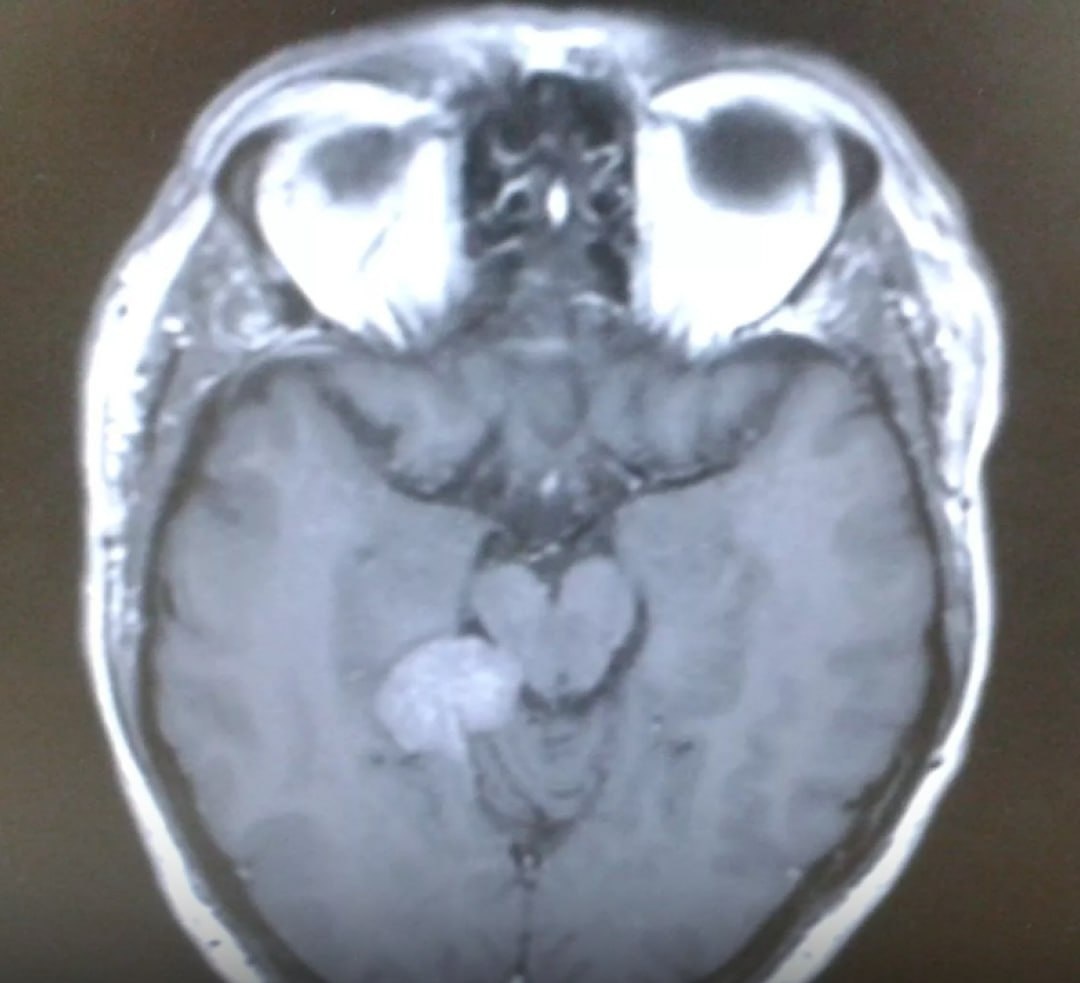

Британский пенсионер, бывший IT-специалист Даррен Харрис на протяжении двух лет страдал от тиннитуса — постоянного звона в ушах. Многочисленные обследования долгое время не выявляли причину жалоб.

🔍 Лишь после консультации нейрохирурга выяснилось: у пациента неоперабельная опухоль головного мозга. Единственным возможным вариантом лечения стала гамма-ножевая радиохирургия.

❗️ Но стойкий односторонний звон, особенно сопровождающийся головной болью, нарушением равновесия, слуха или зрения — повод для углубленного обследования, включая МРТ головного мозга.